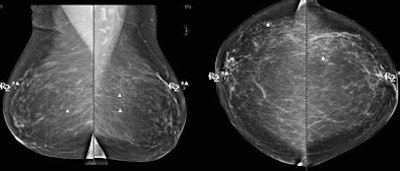

![]() |

| Above, CAD missed the subtle calcification near LCIS while marking several other regions. CAD marked the LCIS lesion on both views in the patient shown below. Images courtesy of Stamatia Destounis, MD. |